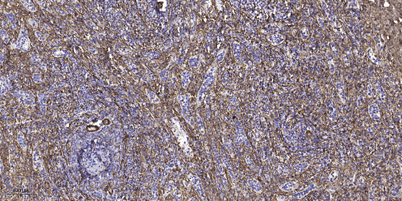

| Product name: | Septin 1 rabbit pAb |

| Dilutions: | Western Blot: 1/500 - 1/2000. Immunohistochemistry: 1/100 - 1/300. ELISA: 1/20000. Not yet tested in other applications. |